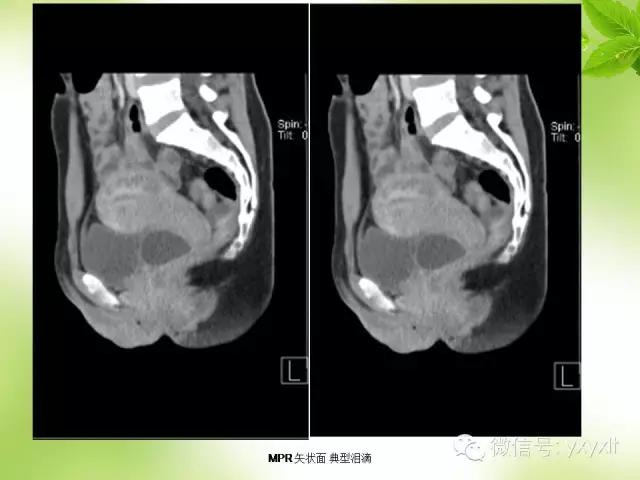

CT:囊肿表现为单房或多房的薄壁水样低密度病灶薄壁囊性肿块,边缘清楚光整。增强扫描未见强化。

病例一